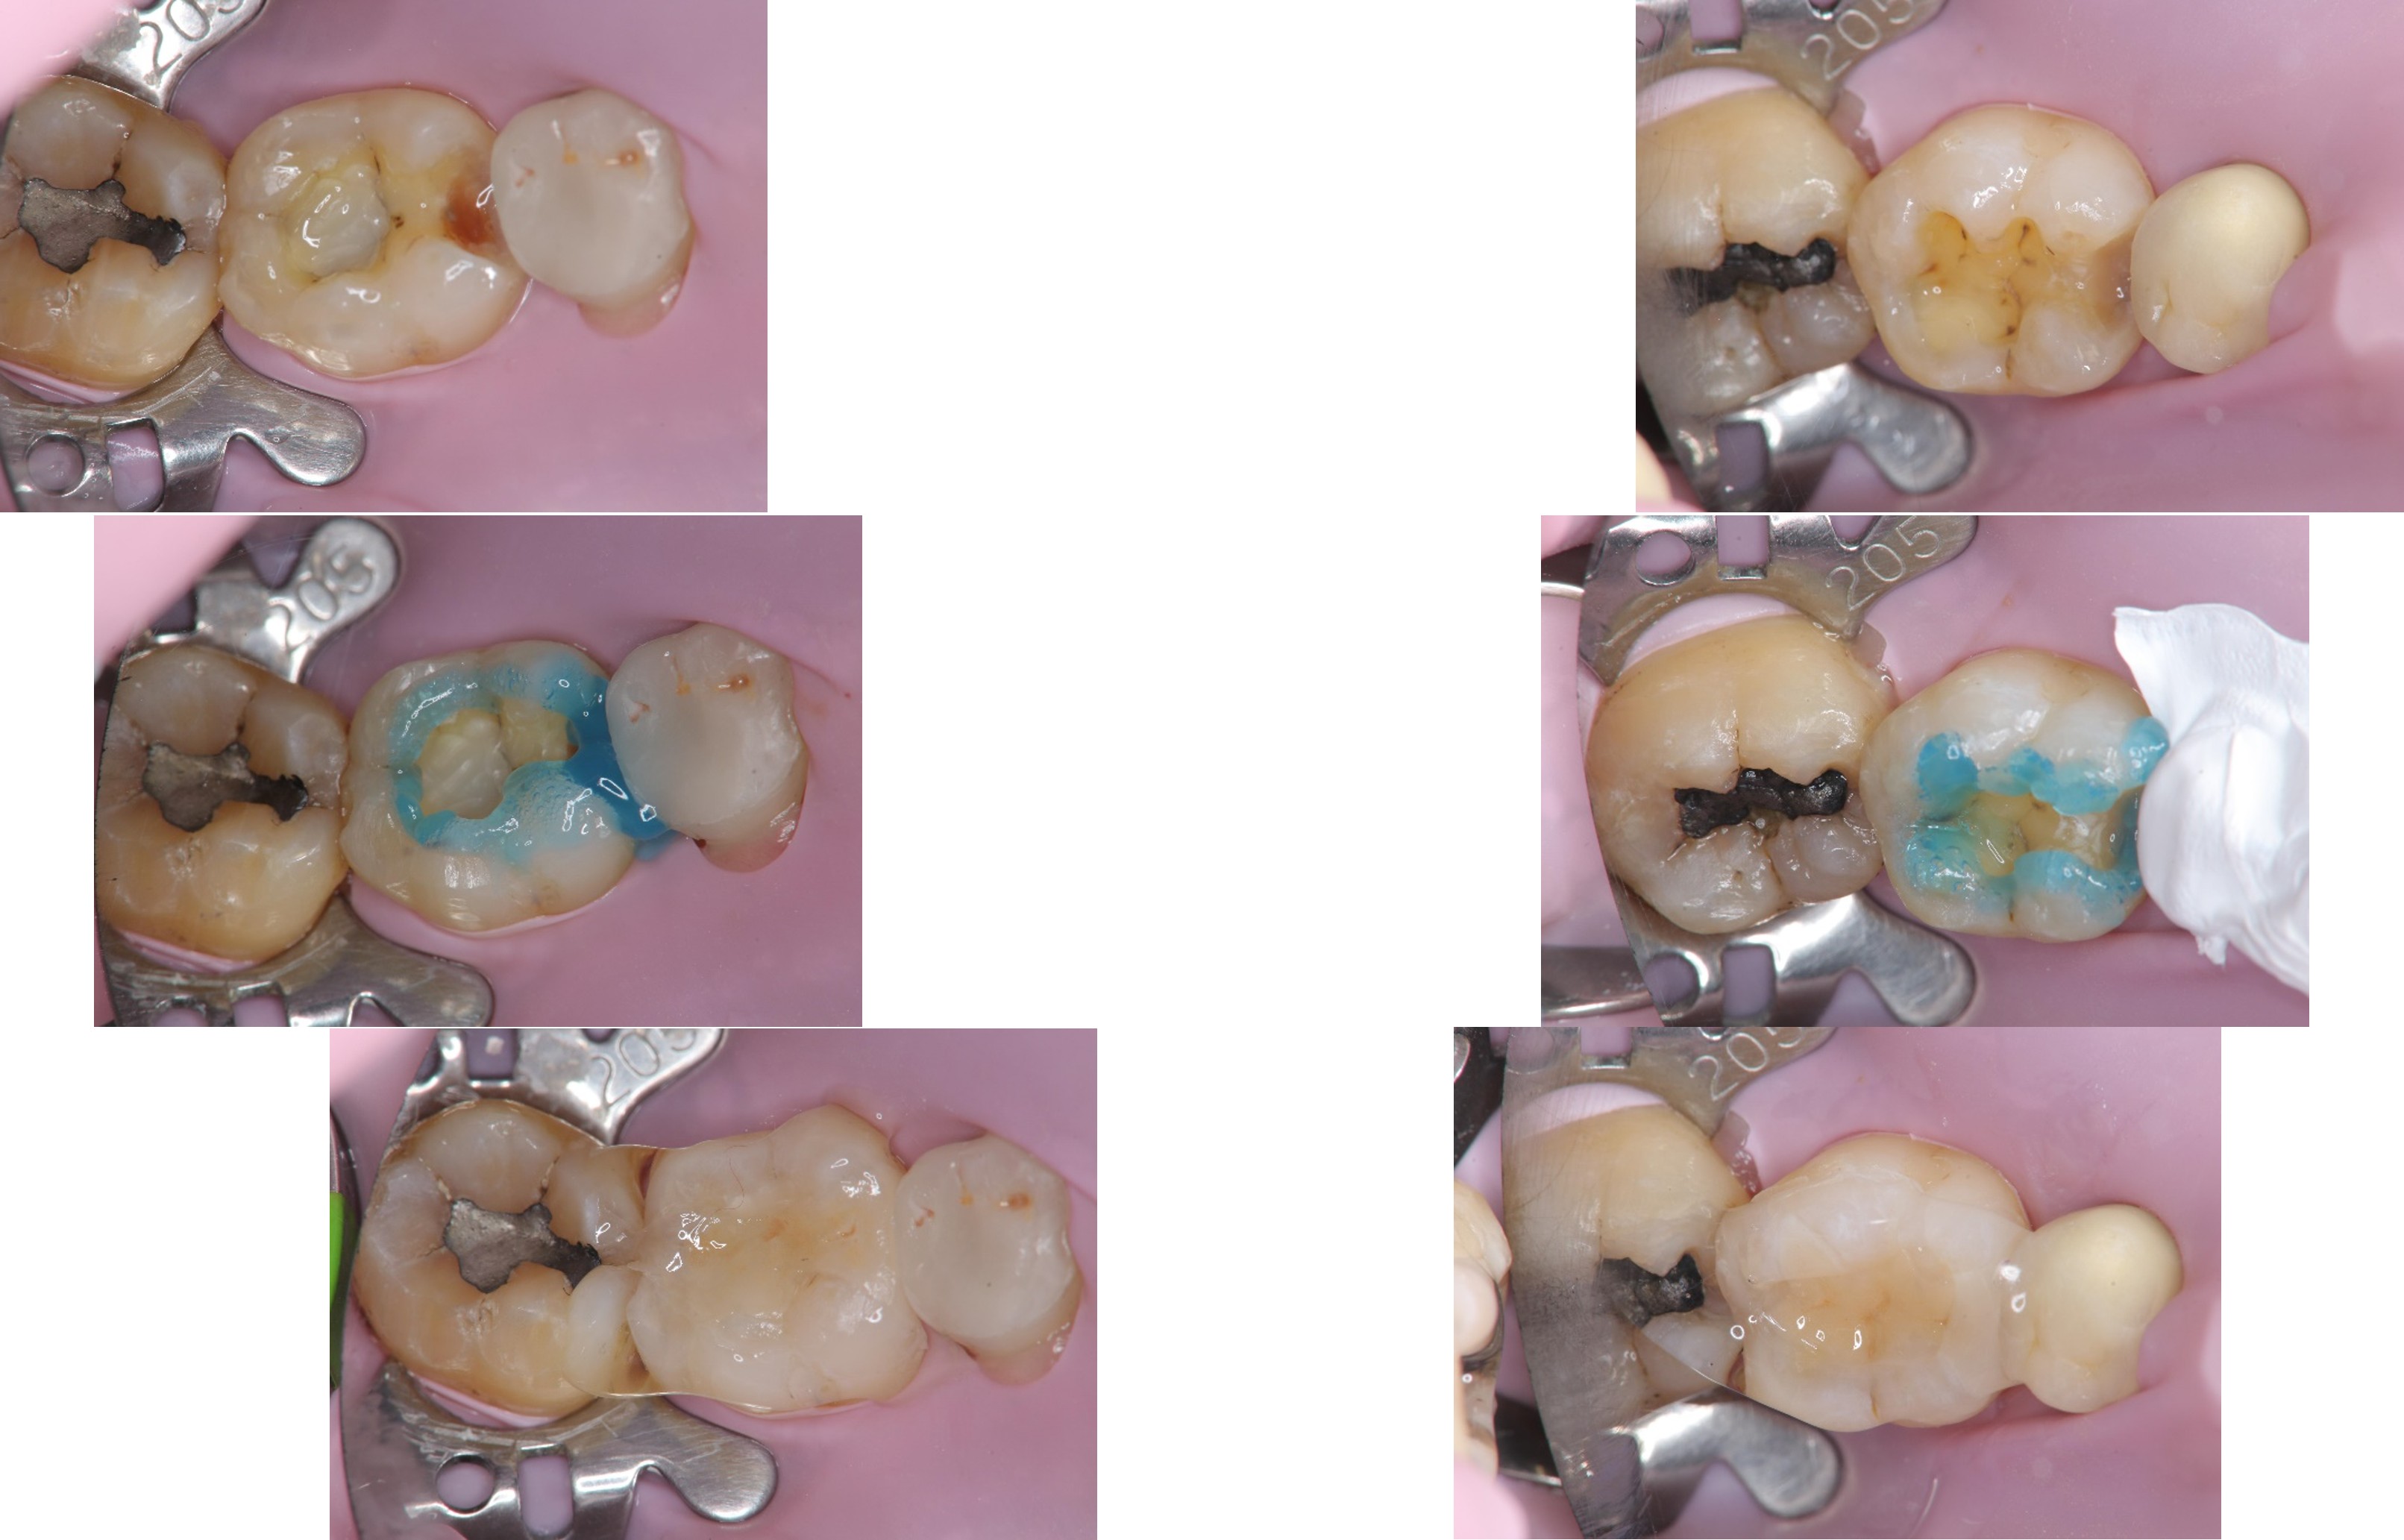

大臼齒的陶瓷崁體

上橡皮障,隔水,黏著瓷塊

術前、術後比較